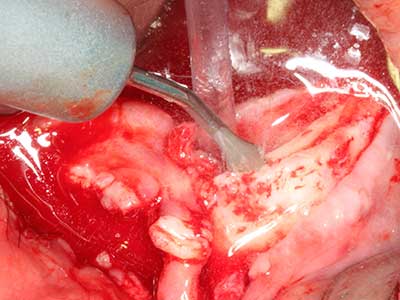

Indication: Preparation near nerves

As noted above, indications for piezo surgery can also be found in the field of conservative dental surgery. Special working tips simplify the exposure of root tips and make it easier to protect nerves and sinus mucous membranes, particularly in the lower premolar and upper posterior tooth regions. Angled diamond tips are used to precisely prepare the resection cavity for the retrograde root filler material for unsealed apical obturation. The ultrasonic technology means the tips can be very slender, which improves the view and the size of the access cavity. As a result, the application of ultrasonic surgery for this indication is one of the standard procedures for apical resection (Del Fabbro, Tsesis et al. 2010, Scarano, Artese et al. 2012).

Indication: Apical resection

When surgical procedures are performed on bone in the immediate vicinity of sensitive structures such as blood vessels or nerves, rotary instruments pose a significant risk of iatrogenic injury. Piezoelectric devices can be helpful for preparation of bone covers and removal of hard tissue close to nerves, particularly for exposure of nerves after iatrogenic injury but also during nerve lateralization for resective and reconstructive procedures or implant placement (Fig. 17-20). Light contact between the piezotip and the nerve does not generally result in damage but proceeding incautiously with saw-like motions or attachments where a residual bone substrate remains may cause temporary or even permanent nerve damage. However, the risk of damage is considered to be substantially lower than when using saws or milling instruments (Pereira, Gealh et al. 2014).